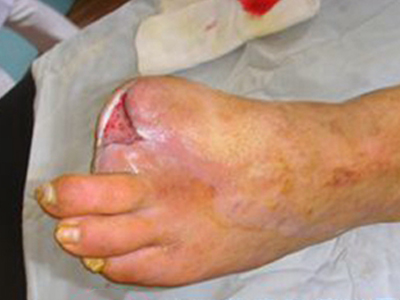

血栓闭塞性脉管炎又称Buerger病,是一种以中、小动脉节段性,非化脓性炎症和动脉腔内血栓形成为特征的慢性动脉闭塞性疾病。主要侵袭四肢,尤其是下肢的中、小动脉和静脉,引起患肢远侧段缺血性病变,出现肢体疼痛、皮肤颜色改变以及坏疽等症状。

血栓闭塞性脉管炎早期肢体发凉、怕冷,逐步出现肢体皮温下降,也可以出现肢体针刺感、烧灼感和麻木等感觉异常。因肢体缺血导致皮色苍白,还可出现皮肤潮红或青紫等表现。患肢还可出现游走性浅静脉炎症状。

肢体缺血可引起程度不同的皮肤干燥、脱屑、患肢肌肉萎缩、肢体变细等。肢端动脉搏动减弱或消失,肢体缺血的最严重后果为肢端坏疽或溃疡。